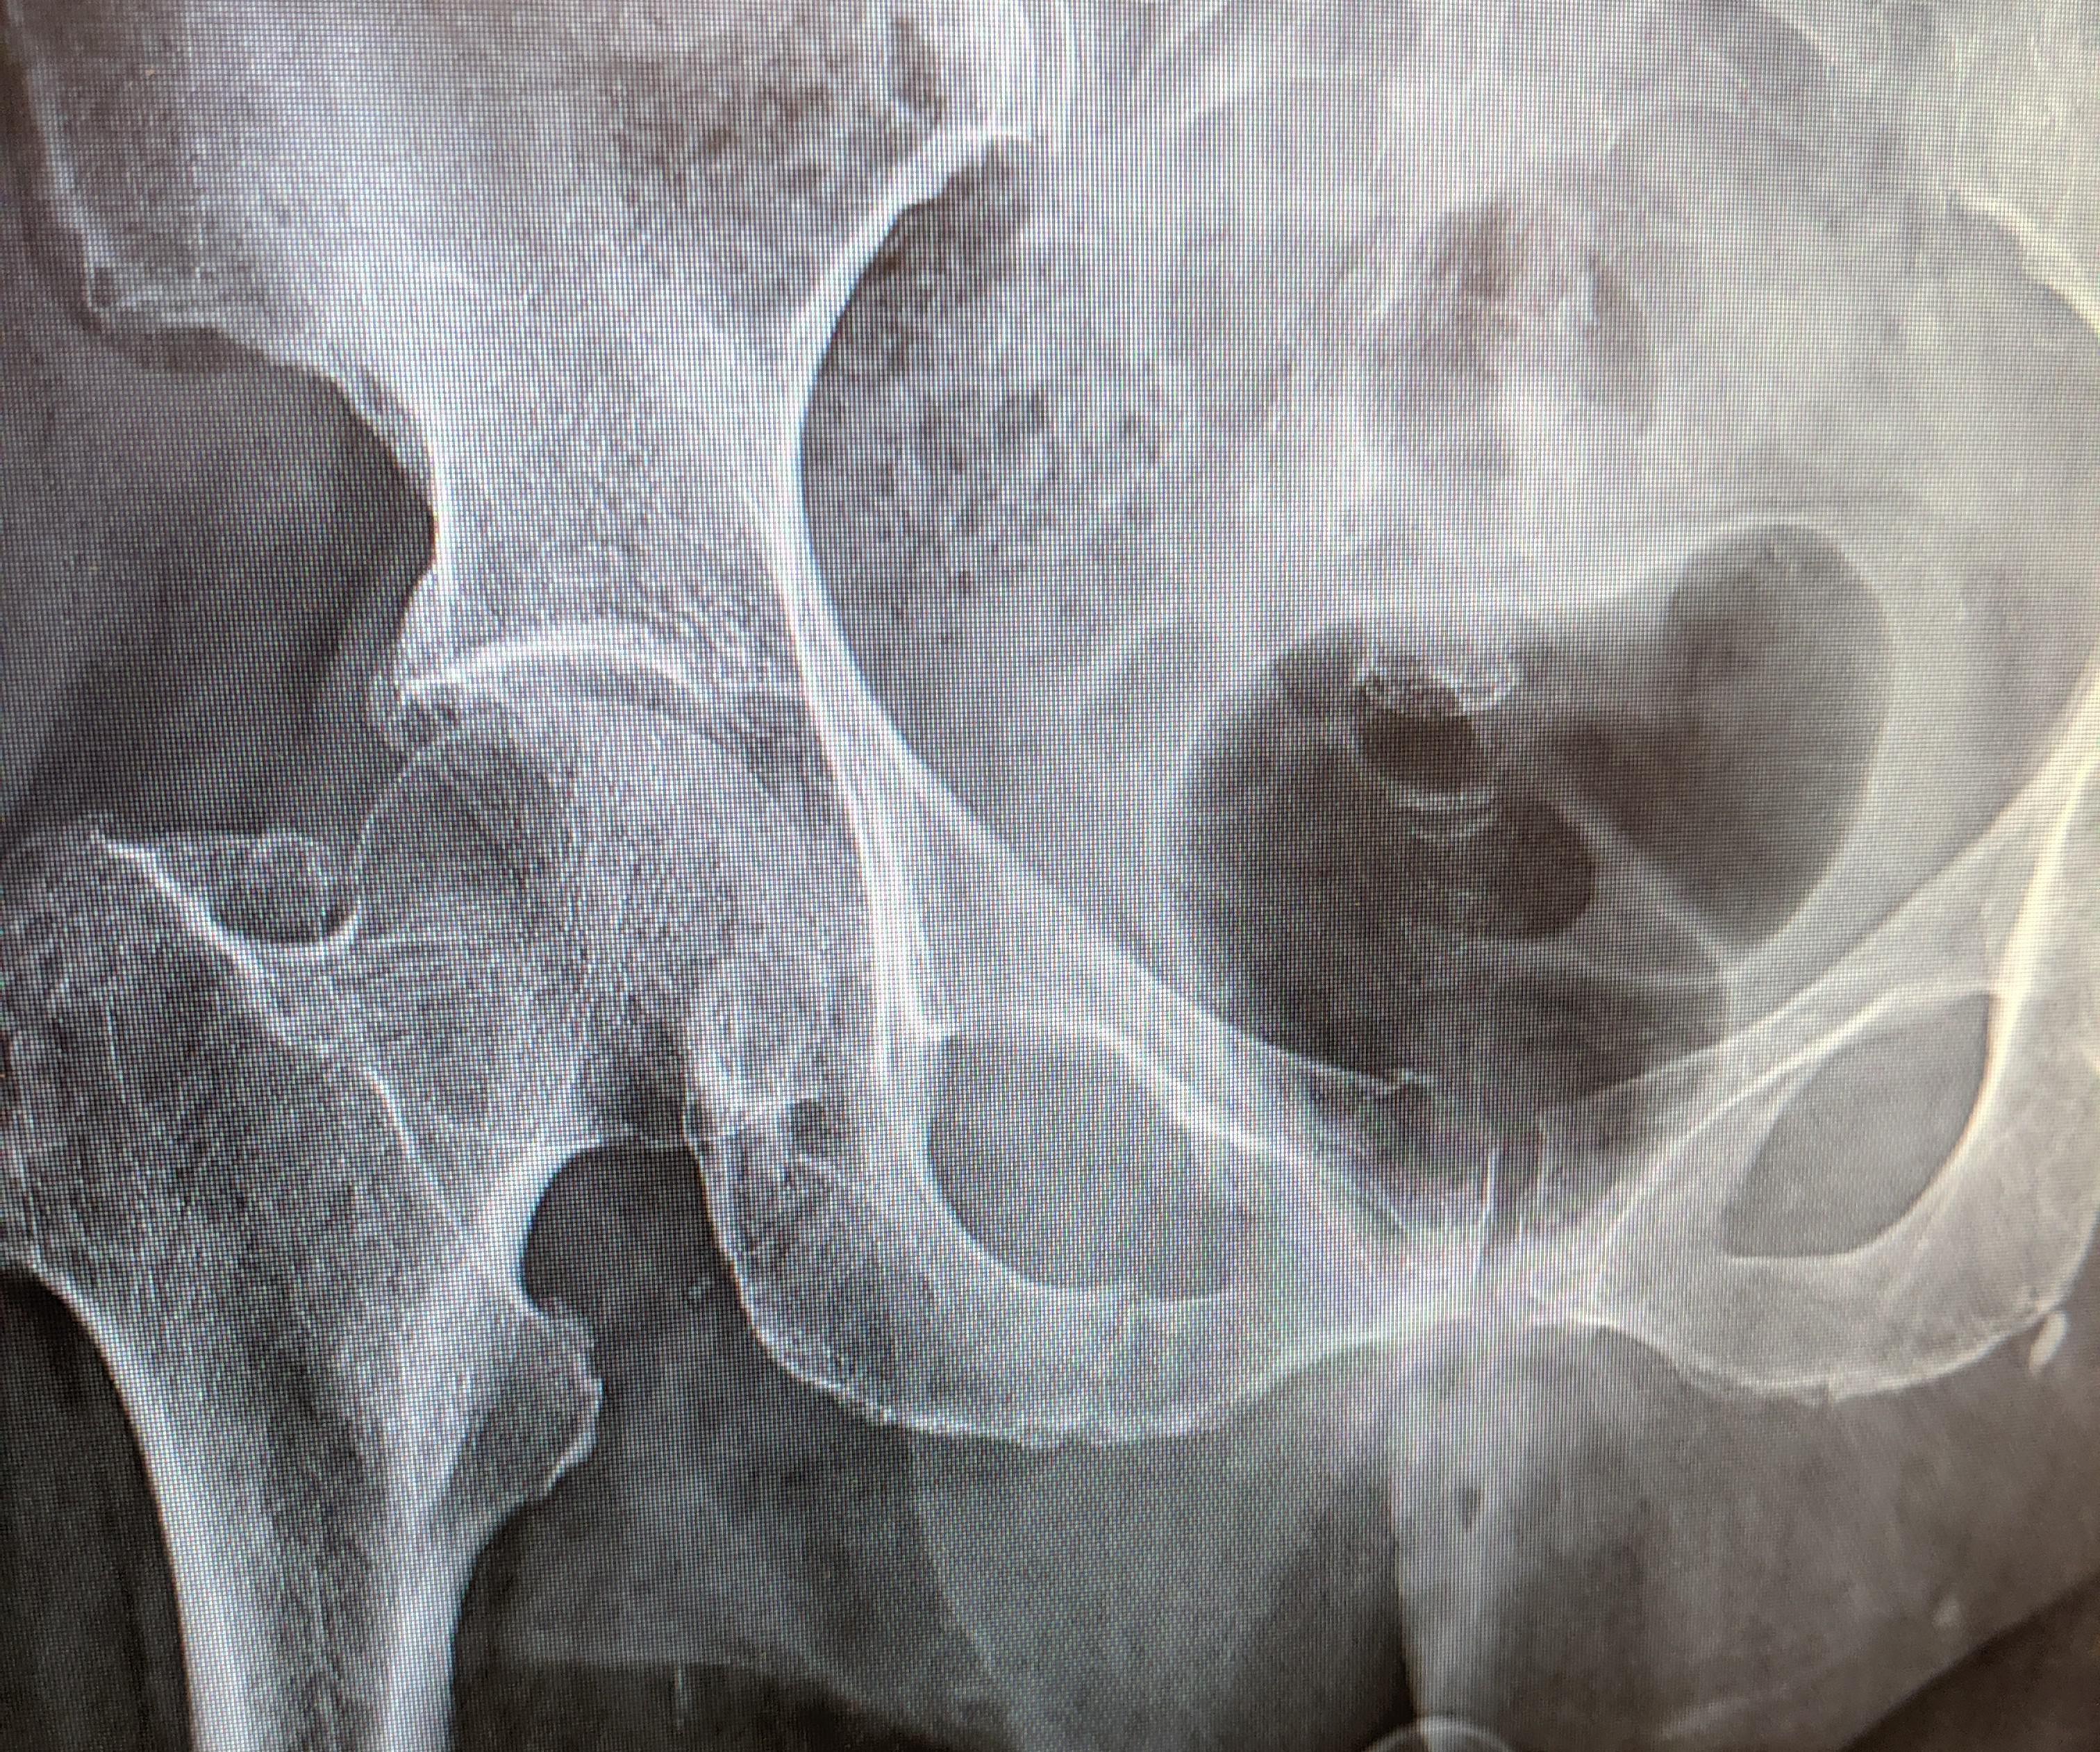

Fracture Of The Pubic Ramus . P ubic ramus fractures and co ncomitant ppri. Higher incidence in males (21%) includes.

Stress fractures of the pubic ramus. Pubic rami fractures do not require surgery and will heal on their own. Introduction we report a case of inferior pubic ramus fracture in a patient with a total hip arthroplasty.

The pubic rami are a group of bones that make up part of the pelvis. Pubic rami fractures are a subgroup of pelvic fractures. Superior and inferior pubic ramus fracture. 1, 2, 3 current literature continues to describe this injury as a pelvic fracture. Localised pain in the pelvis or pelvic area.

In all of the patients the fracture was in the inferior pubic ramus near the symphysis pubis, and caused pain in the groin, buttock, or thigh. Hill rm, robinson cm, keating jf. Pubic rami fractures do not require surgery and will heal on their own. Pelvic fracture should be suspected in any polytrauma patient particularly where there is. In at.

They can range in severity from relatively benign injuries to life. This bone tends to break on the top and the bottom of the ring. In all of the patients the fracture was in the inferior pubic ramus near the symphysis pubis, and caused pain in the groin, buttock, or thigh. Pubic ramus fractures occur as parasymphysial fractures, midramus fractures,.